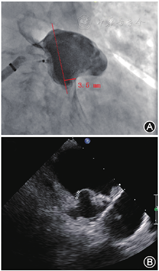

旋开止血阀回拉释放手柄数厘米,确认钢缆与封堵器连接良好。首先进行近端排气,输送系统远端浸没于肝素盐水中,助手用手指轻轻堵住输送系统远端,用50 ml螺口注射器在输送系统Y阀注射肝素盐水,近端连续出水完成排气后,持续注射肝素盐水同时旋紧止血阀;然后进行远端排气,助手松开输送系统的远端,保持其完全浸没于肝素盐水中,在Y阀处以"慢抽快冲"的方式注射肝素盐水,冲洗2~3次,保留30~ 40 ml肝素盐水于螺口注射器内,完成排气。最后使封堵器远端对齐输送系统标记环,若左心耳可用深度受限时,可体外借深度,即使封堵器远端超出标记环1~2 mm,建议不超过3 mm(图3)。